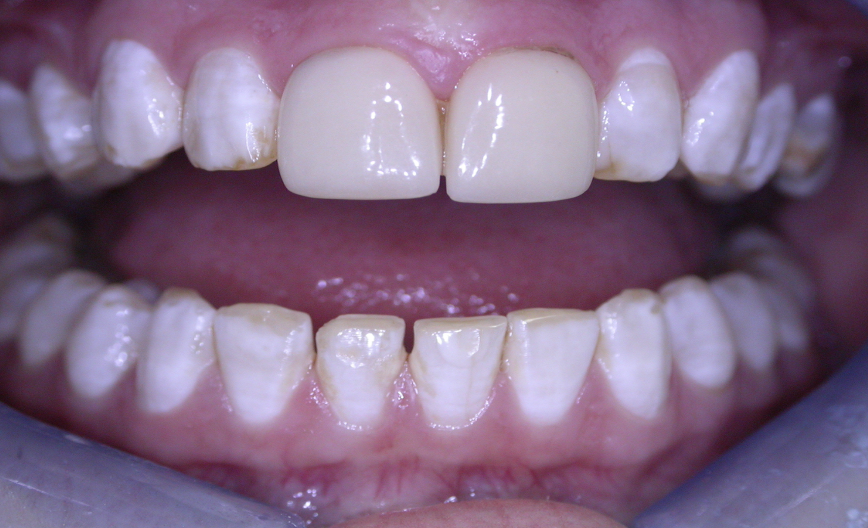

<p>outline notable points about this patient</p>

outline notable points about this patient

• centrals are a different colour to the rest of the dentition

• mottling of enamel makes upper centrals look like this

• calculus between lower anteriors

• class IV on disto-incisal of LR1